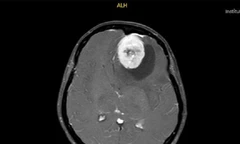

Cứu bệnh nhân bị khối u khủng kéo sụp tai xuống cổ

Sức khỏe

TPO - Mang trong mình khối u sợi thần kinh bẩm sinh hiếm gặp từ khi chào đời, nam thanh niên 24 tuổi ở Vĩnh Long phải sống chung với tình trạng biến dạng nghiêm trọng vùng mặt, tai và cổ. Các bác sĩ Bệnh viện Chợ Rẫy đã thực hiện ca phẫu thuật phức tạp, bóc tách khối u nặng gần 1kg, giúp người bệnh cải thiện sức khỏe và diện mạo.